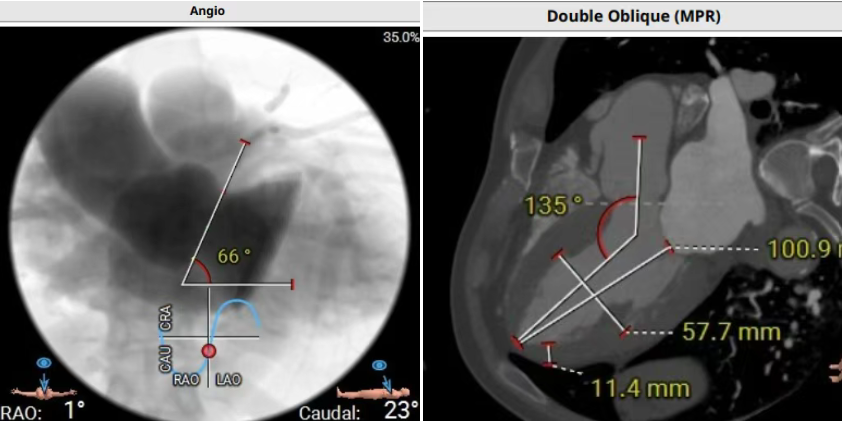

術前CT評估提示,患者主動脈瓣三葉瓣,瓣葉增厚,舒張期右冠瓣脫垂,右冠瓣瓣葉輕度鈣化,存在三個瓣竇,分布較均勻;主動脈瓣環周長折算直徑28.0mm;左心室流出道周長折算直徑29.5mm,無鈣化,無狹窄;STJ直徑35.3mm,升主動脈直徑41.8mm;雙側冠脈開口高度可LCA13.5mm ,瓣葉長17.2mm;RCA33.9mm,瓣葉長10.0mm;側左冠脈輕度鈣化;橫位心,左室主動脈夾角為135°;